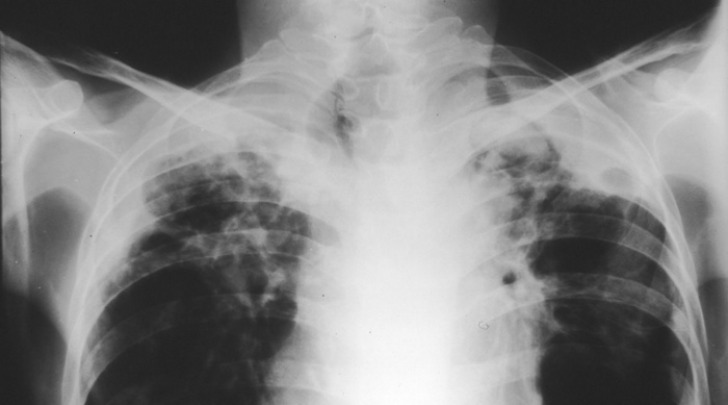

Essendo la TBC una malattia infettiva, occorre fare molta attenzione per individuarla il prima possibile: la tubercolosi attacca solitamente i polmoni, ma puo' colpire anche altre parti del corpo.

I sintomi classici sono tosse cronica con espettorato striato di sangue, febbre di rado elevata, sudorazione notturna e perdita di peso.